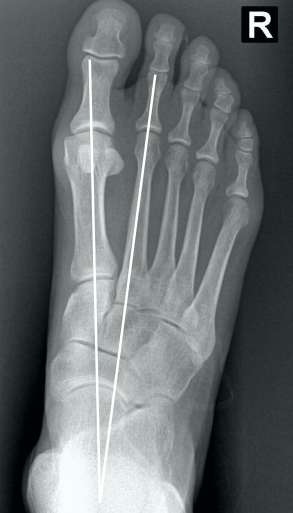

• Na radiografia em AP com carga, como é traçado o ângulo intermetatarsal?

• Ângulo entre o eixo longo do 1° e do 2° raio

• Normal → até 9°

• Leve → 9° a 12°

• Moderado → 13° a 15°

• Grave → > 16°

• Na radiografia em AP com carga, como é traçado o ângulo de valgismo do hálux (metatarsofalângico)?

• Ângulo entre o eixo longo do 1° mtt e o eixo longo da falange proximal

• Normal → até 15°

• Leve → < 25°

• Moderado → 25° a 40°

• Grave → > 40°